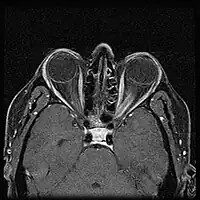

MRI of a patient with ONSM

The most common symptom of ONSM is a gradual loss of vision in one eye. In a minority of patients this may be intermittent, at least to begin with. Less common symptoms include pain in the affected eye, protrusion of the eye, or double vision.[2]

When ONSM is suspected, MRI of the brain or orbits should be performed. This will usually show characteristic findings and confirm the diagnosis.[5]